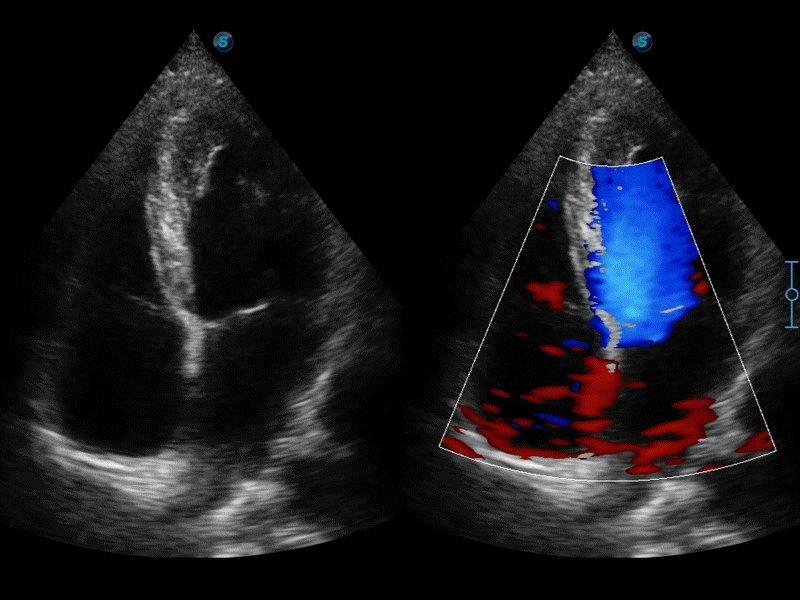

自动识别前后壁内膜厚度,为心血管疾病早期评估提供快速准确依据。

自动识别收缩和舒张末期心肌内膜,自动计算射血分数EF值。